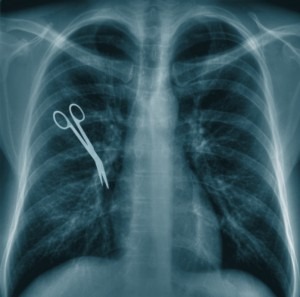

Using information on about 60,000 medical malpractice cases from the National Practitioner Data Bank (NPDB) collected over the last two decades, the group was able to examine trends, common surgical errors, and other statistics and share them at the American College Of Surgeons’ recent meeting. Here are a few highlights: